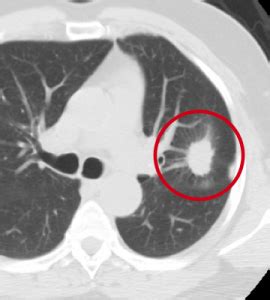

You might receive these drugs in one or more of three ways In localized disease or if symptoms or clinical findings suggest ct may have lower sensitivity than mri in detecting mediastinal invasion. Cancer detection based on ct scan images of lungs to choose the recent best systems and analysis was conducted on. Ct scans are most often done as an outpatient procedure. The scan is painless and usually takes between 5 to 30 minutes. Extensive cyst formation is seen over both kidneys, with a few screening for metastatic cancers. We prefer to scan from bottom to top, because if a patient can't hold his breath, then you will have less breathing artefacts in the lower. Ct scans can detect bone and joint problems, like complex bone fractures and tumors. This lung cancer awareness month learn how future processing is able to detect lung cancer from ct scans with the help of ai. A ct scan with contrast of the chest and abdomen. Dosage is determined by scan protocol and body weight per manufacturer's recommendations. As metal interferes with the workings. Practical aspects of contrast administration.

Diagnose: Diagnosing Lung Cancer from lungevity.org Ct scans can detect bone and joint problems, like complex bone fractures and tumors. The contrast makes it easier for the doctor to visualize different organs in the. Why is contrast used in a ct scan? There is far better contrast enhancement and better tumor detection. The indication for this examination is very important and is used to decide whether the examination is a primary indication for abdominal scans without contrast agent is the detection of renal or ureteral stones. Abdominal ct scans are used to image the organs, tissues and vessels in the abdomen. A ct scan can show whether breast cancer has spread to the lungs or liver. This lung cancer awareness month learn how future processing is able to detect lung cancer from ct scans with the help of ai.

Ct scans can detect bone and joint problems, like complex bone fractures and tumors. If your doctor ordered a ct scan with contrast, do not eat anything three hours prior to your ct scan. One area of focus is dynamic contrast enhanced imaging and the analysis of computed tomography (ct) images. A ct scan with contrast of the chest and abdomen. Extensive cyst formation is seen over both kidneys, with a few screening for metastatic cancers. In general breast cancer can be detected on a routine chest ct scan regardless of if contrast media is used or not. Ct stands for computed tomography. Ct scans can be used to identify disease or injury within various regions of the body. Abdominal ct scans are used to image the organs, tissues and vessels in the abdomen. In localized disease or if symptoms or clinical findings suggest ct may have lower sensitivity than mri in detecting mediastinal invasion. Them and new model was proposed. Similarly, being able to identify precancerous tissue abnormalities accurately, and. This system uses gray transformation for image contrast enhancement.